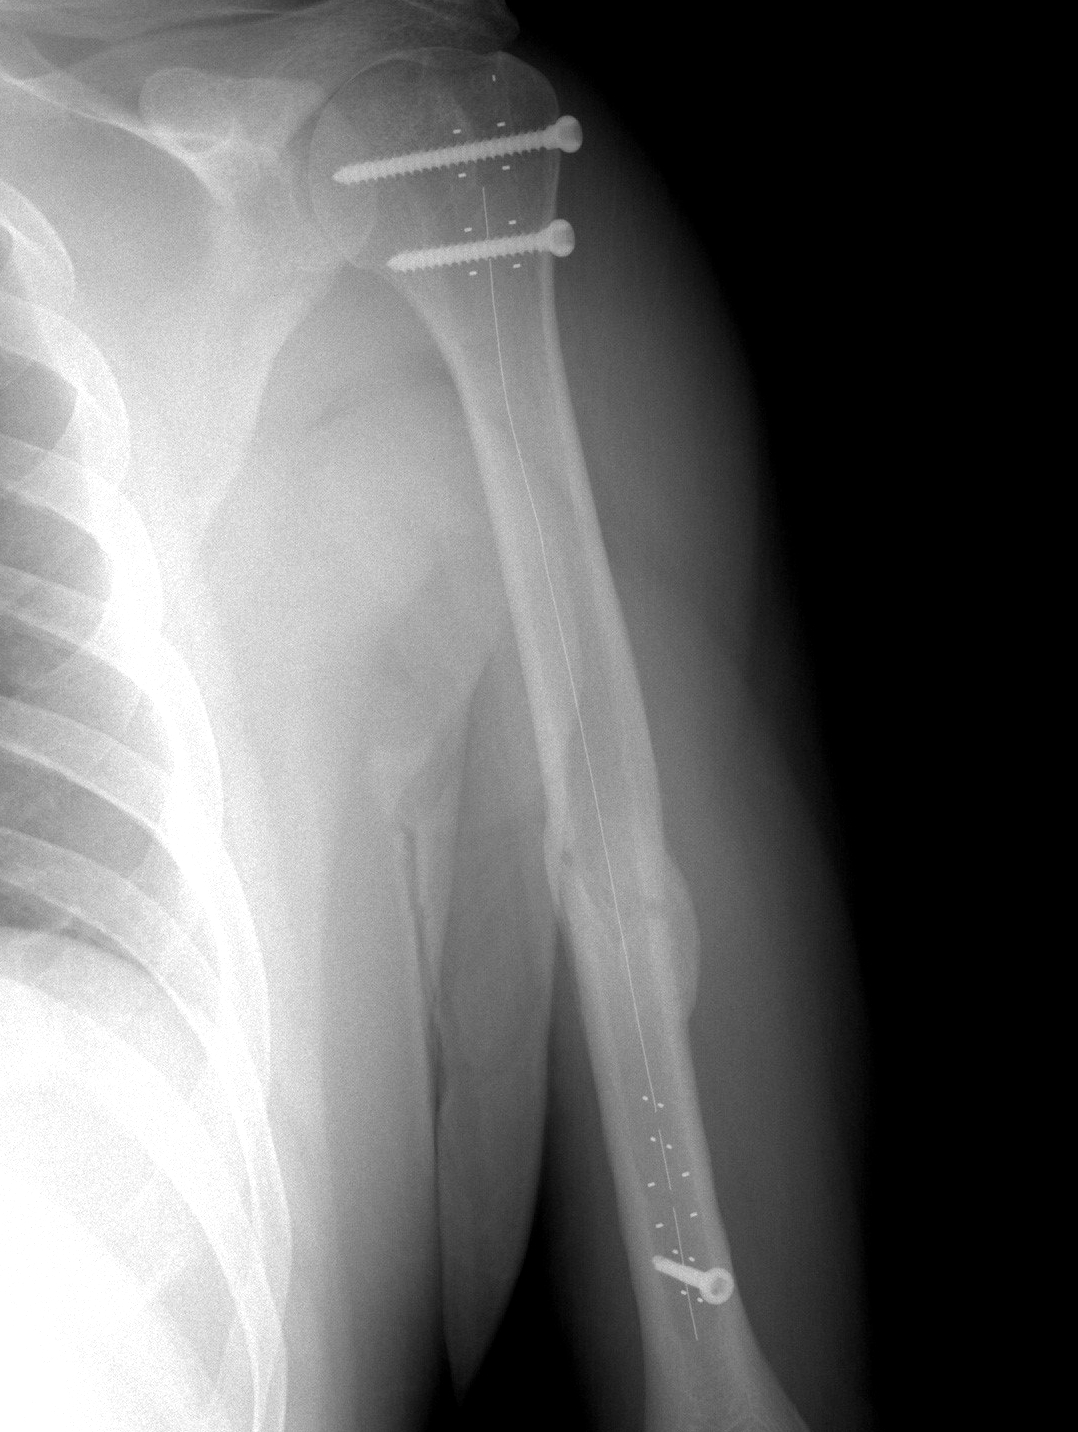

Нарост На Плечевой Кости Фото

Нарост На Плечевой Кости Фото 147 фотографий